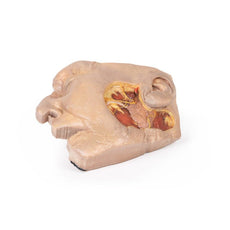

The head and neck of the specimen provides views of both superficial and deep structures in the region. The calotte has been removed ~2cm superior to the orbits to expose the brain in relation to the endocranial cavity. The transverse section through the cerebrum demonstrates the relation of the grey matter cortex to the white matter medulla, as well as the lateral ventricles with a small amount of choroid plexus visible in the base of both spaces. The skin and superficial fascia on the right side has been retained and false-coloured to display the angiosomes of the face and posterior neck. On the left side, the superficial tissues have been dissected to expose the muscles of facial expression, muscles of mastication, and deeper structures of the infratemporal fossa including the lingual nerve, terminal branches of the external carotid artery into the superficial temporal and maxillary arteries.

The head and neck of the specimen provides views of both superficial and deep structures in the region. The calotte has been removed ~2cm superior to the orbits to expose the brain in relation to the endocranial cavity. The transverse section through the cerebrum demonstrates the relation of the grey matter cortex to the white matter medulla, as well as the lateral ventricles with a small amount of choroid plexus visible in the base of both spaces. The skin and superficial fascia on the right side has been retained and false-coloured to display the angiosomes of the face and posterior neck. On the left side, the superficial tissues have been dissected to expose the muscles of facial expression, muscles of mastication, and deeper structures of the infratemporal fossa including the lingual nerve, terminal branches of the external carotid artery into the superficial temporal and maxillary arteries.